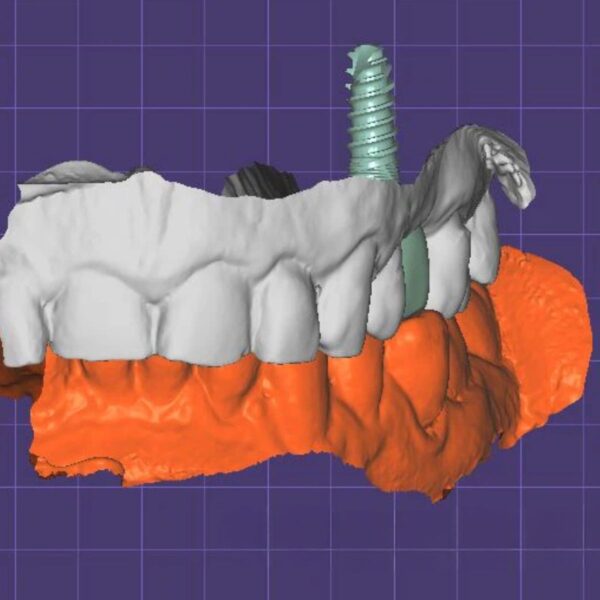

- ✓ ASC Technology: Angulated Screw Channels (up to 25°) to hide access holes.

- ✓ Passive Fit: Perfect cement gap settings for Ti-Base bonding.

- ✓ Tissue Health: Custom emergence profile to shape the gingiva.

Compatible with: Nobel, Straumann, Zimmer, BioHorizons, etc.